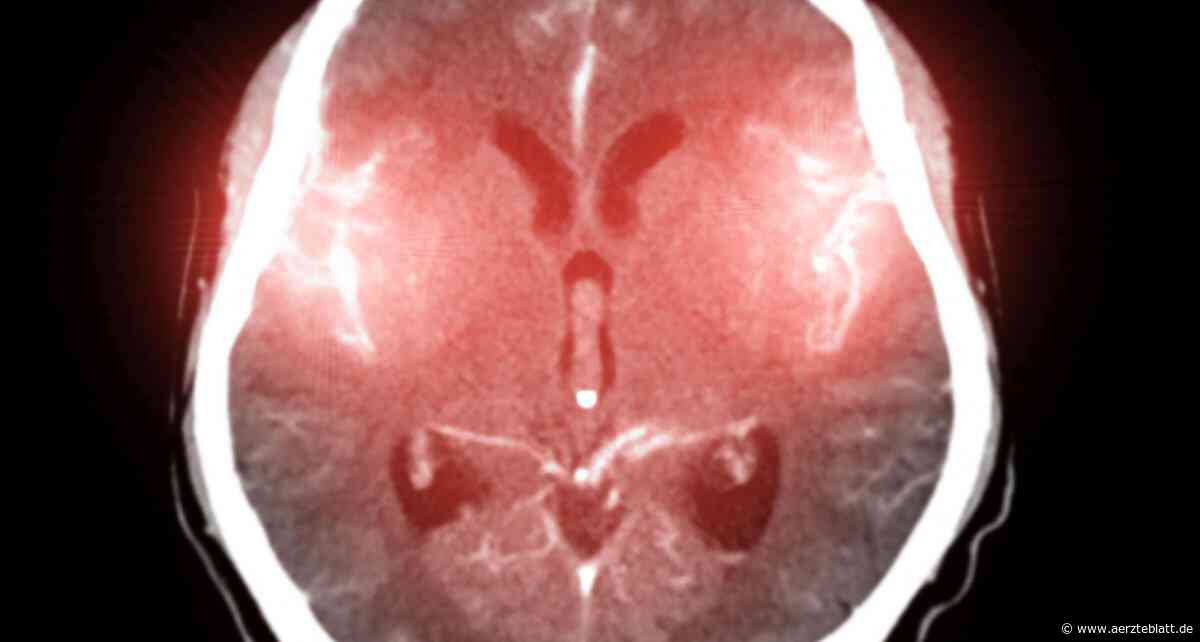

Zerebralen Mikroangiopathie unterscheidet sich bei Frauen und Männern

Hirnaneurysma: Bluttransfusionen können Behandlungsergebnisse von Subarachnoidalblutungen verbessern